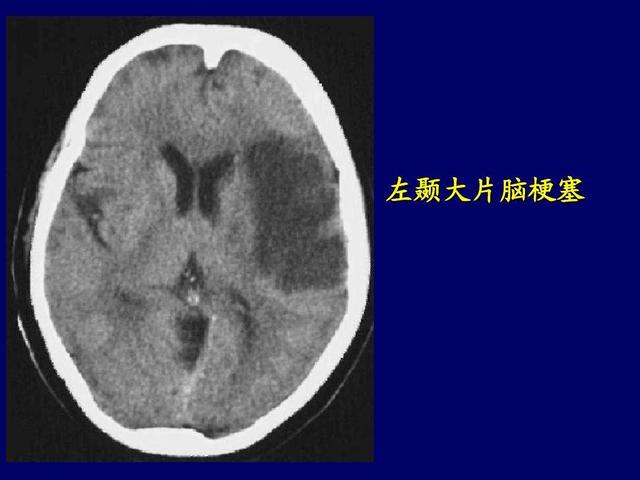

不过就在前几天马大哥整理餐具的时候却突然晕倒 , 这可把妻子吓坏了 , 于是赶紧拨打了120送往了医院 , 后来经过医生的检查得知 , 没想到47岁的马大哥竟然患上了脑梗 , 这让夫妻两个人的生活如同雪上加霜 。 马大哥也是非常的疑惑 , 自己平时饮食还不错 , 身体还是比较健壮的 , 怎么会突然患上脑梗呢?后来经过与医生的交谈 , 得知原来正是因为马大哥爱吃肉的原因 。